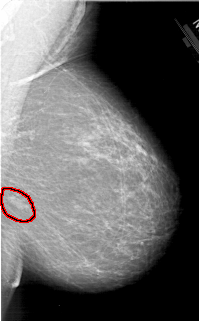

A_1321_1.RIGHT_CC

RIGHT_CC LINES 5836 PIXELS_PER_LINE 3766 BITS_PER_PIXEL 12 RESOLUTION 43.5 OVERLAY

FILE: A_1321_1.RIGHT_CC.OVERLAY

TOTAL_ABNORMALITIES 1

ABNORMALITY 1

LESION_TYPE MASS SHAPE OVAL MARGINS CIRCUMSCRIBED

ASSESSMENT 4

SUBTLETY 3

PATHOLOGY BENIGN

TOTAL_OUTLINES 1

BOUNDARY